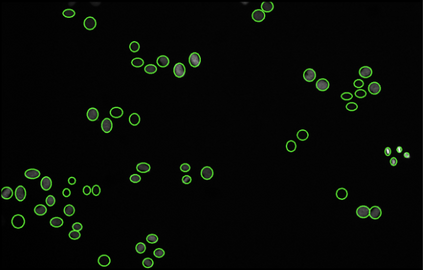

Cell detection in microscopy images is important to study how cells move and interact with their environment. Most recent deep learning-based methods for cell detection use convolutional neural networks (CNNs). However, inspired by the success in other computer vision applications, vision transformers (ViTs) are also used for this purpose. We propose a novel hybrid CNN-ViT model for cell detection in microscopy images to exploit the advantages of both types of deep learning models. We employ an efficient CNN, that was pre-trained on the ImageNet dataset, to extract image features and utilize transfer learning to reduce the amount of required training data. Extracted image features are further processed by a combination of convolutional and transformer layers, so that the convolutional layers can focus on local information and the transformer layers on global information. Our centroid-based cell detection method represents cells as ellipses and is end-to-end trainable. Furthermore, we show that our proposed model can outperform fully convolutional one-stage detectors on four different 2D microscopy datasets. Code is available at: https://github.com/roydenwa/cell-centroid-former